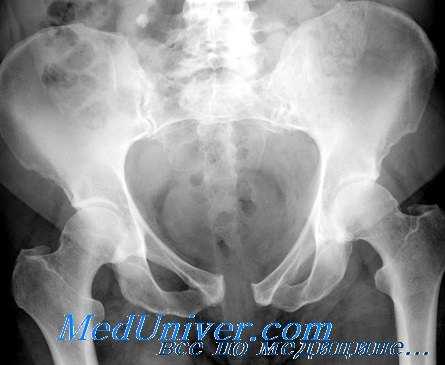

Рентгенограмма при переломе костей таза

- Рентгенография костей таза.